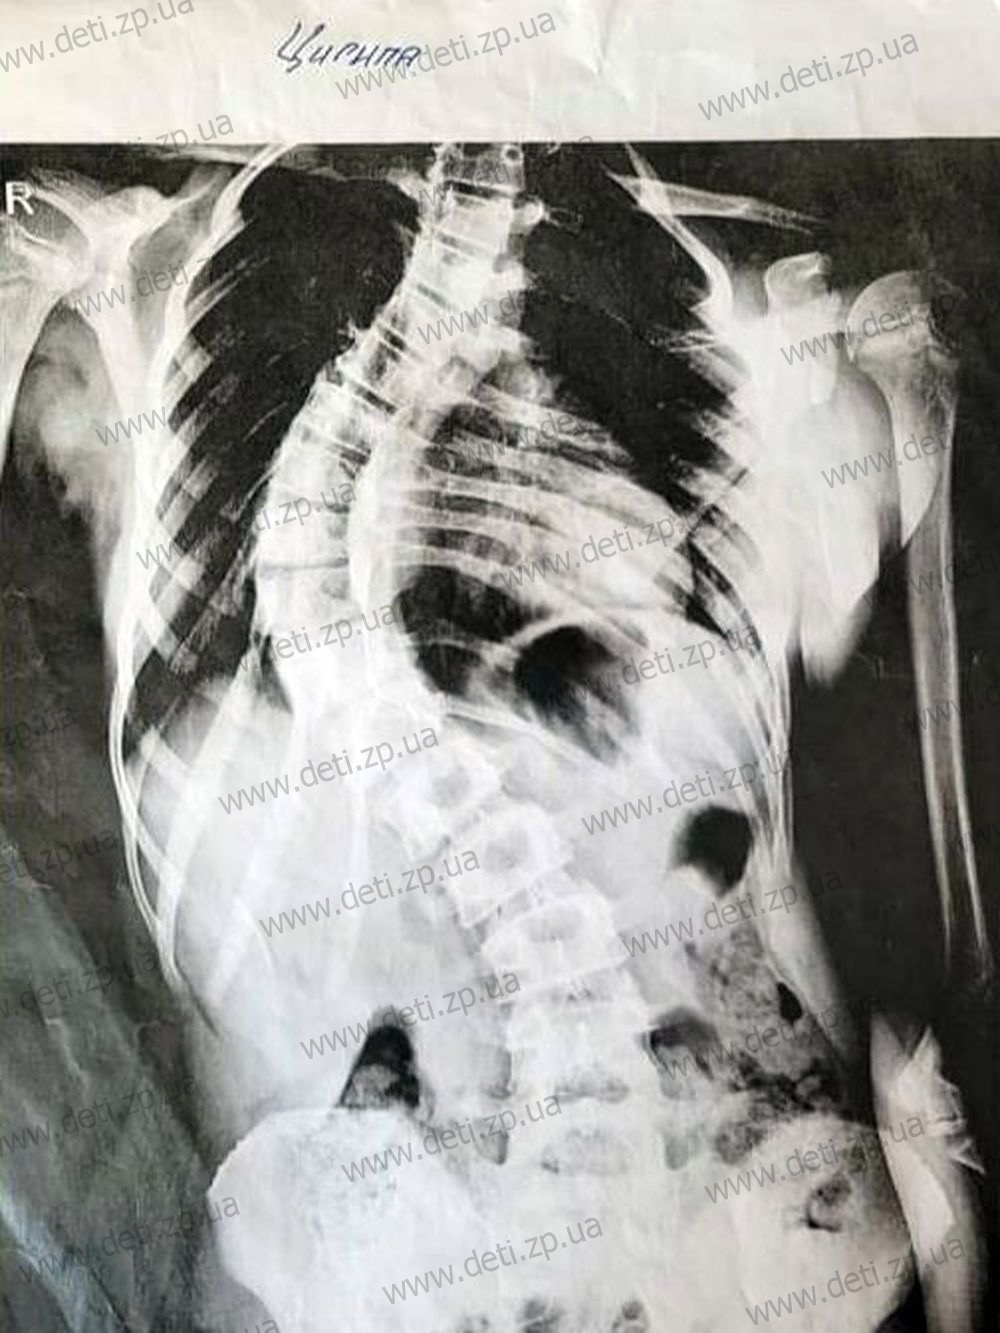

Diagnosis: Severe scoliosis.

Despite two years of conservative treatment and wearing a brace, Daryna’s condition has only worsened. Doctors at Okhmatdyt hospital have recommended surgery to implant special devices that will help align and stabilize her spine. The cost of these implants is 274,800 UAH — a huge sum for Daryna’s family, as her mother works as a nurse and her father is a firefighter.